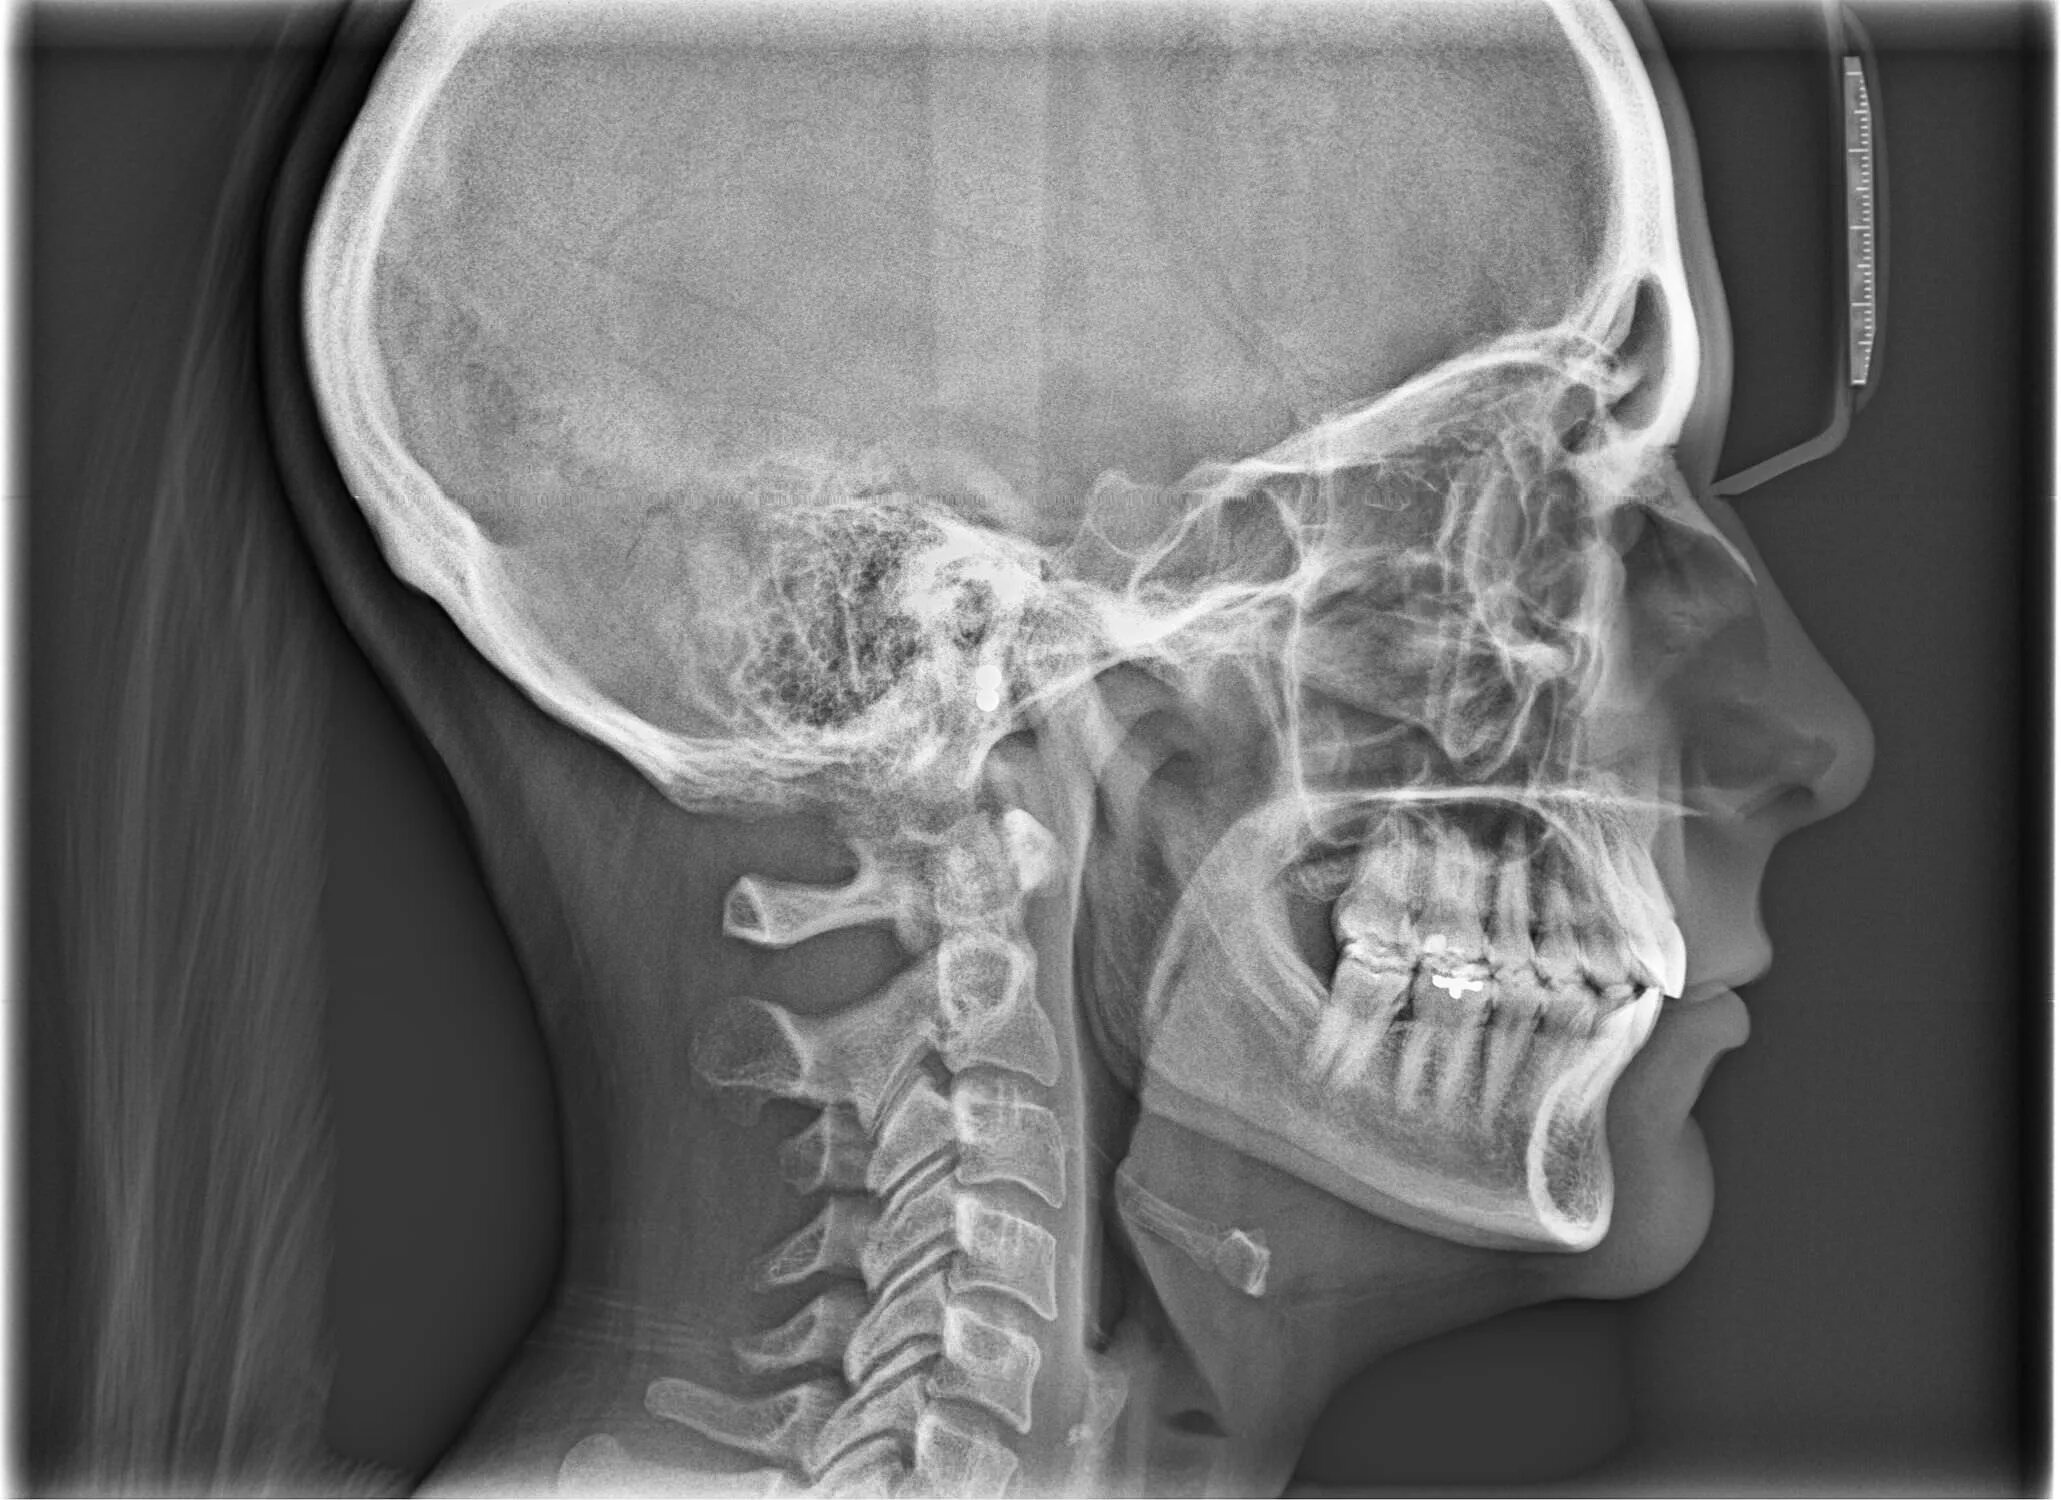

Трг проекции